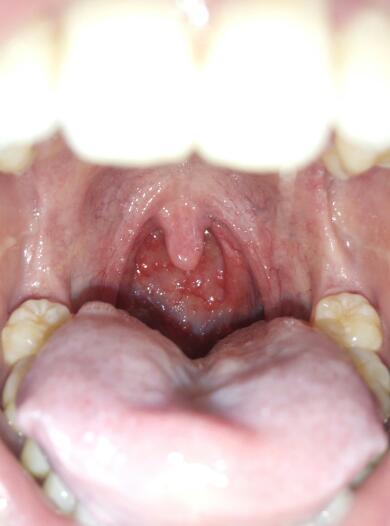

喉咙里面有小疙瘩

喉咙里面有小疙瘩,正常喉咙

正常喉咙

咽喉深处长满小颗粒

发炎扁桃体图片

咽喉息肉图片

喉咙息肉的症状图片

喉咙里面有小疙瘩图片

正常喉咙图片对比

喉咙正常与发炎图片